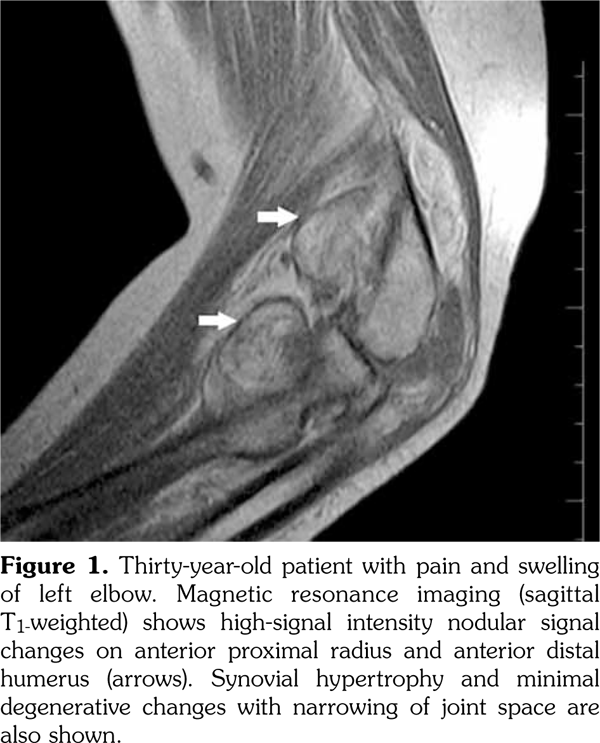

Magnetic resonance imaging of the left elbow (Figure 1) was performed and T1-weighted MRI showed high-signal intensity, while the short tau inversion recovery images showed isointensity with fat nodular signal changes on the anterior of proximal radius and distal humerus, respectively. MRI of the right wrist demonstrated synovial hypertrophy and effusion in the radioulnar and intercarpal joints. For exact diagnosis and treatment, open synovectomy of the left elbow was performed. Histopathological examination of the specimen (Figure 2) showed infiltration of the subsynovial space with mature adipocytes (hematoxylin and eosin stain x 40) and the diagnosis was reported as LA.

Histopathological appearance is the papillary villi infiltrated with mature fat cells.(1) Mononuclear chronic inflammatory cells may be seen in the overlying synovial membrane and the synovial cells may be reactive with eosinophilic cytoplasm.(1) In our patient, subsynovial space was infiltrated with mature adipocytes.